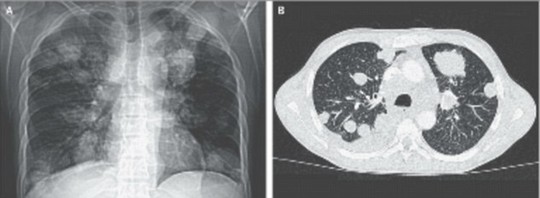

Các u hạch ung thư xuất hiện trong gan, phổi, tuyến thượng thận người đàn ông

Năm 2013, một người đàn ông 41 tuổi (giấu tên) nhiễm HIV tìm đến các bác sĩ tại Bệnh viện Medellin, Colombia trong trạng thái mệt mỏi vì sốt, ho và giảm cân trong nhiều tháng. Tại đây, ông được thông báo có khối u đường kính khoảng 4 cm trong phổi và nhiều nơi khác trong cơ thể. Các bác sĩ phát hiện những khối u xuất phát từ các tế bào của sán dây. Các chuyên gia y tế tin rằng do hệ miễn dịch của người đàn ông đã suy yếu nên đã tạo điều kiện cho sán dây sống trong cơ thể và phát triển thành bệnh ung thư.

Trước đó, khi xét nghiêm phân của nam bệnh nhân, các bác sĩ phát hiện nhiều trứng sán Hymenolepis nana (còn gọi là sán dây lùn vì nó hiếm khi phát triển dài hơn 40 mm và tròn 1 mm). Kết quả CT scan cho thấy bệnh nhân còn bị các khối u ung thư trong phổi từ 0.4 - 4,4 cm. Đồng thời, các khối u cũng đã lan sang gan, tuyến thượng thận và những bộ phận lân cận. Kết quả sinh thiết khối u phổi của người đàn ông cho thấy hiện tượng kỳ lạ: Các khối u ung thư tồn tại nhưng các tế bào lại rất nhỏ. “Chúng nhỏ hơn so với tế bào ung thư của con người 10 lần”, TS Muehlenbachs nói. Các nhà nghiên cứu cũng nhận ra các tế bào u cũng nằm lộn xộn, chen chúc - điều không thường thấy trong các tế bào của con người.